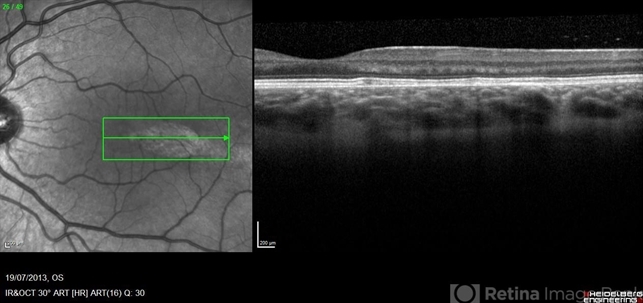

- Torpedo maculopathy

- Optical coherence tomography system

- SD-OCT through lesion at posterior pole of asymptomatic 8-year-old female.